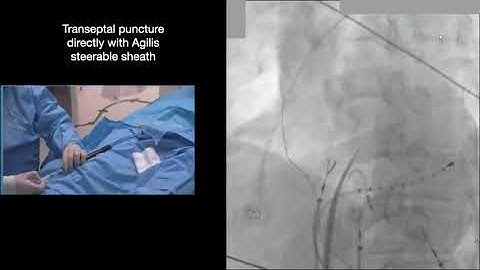

How to echocardiographically guide a trans-septal puncture - PITLOC Protocol